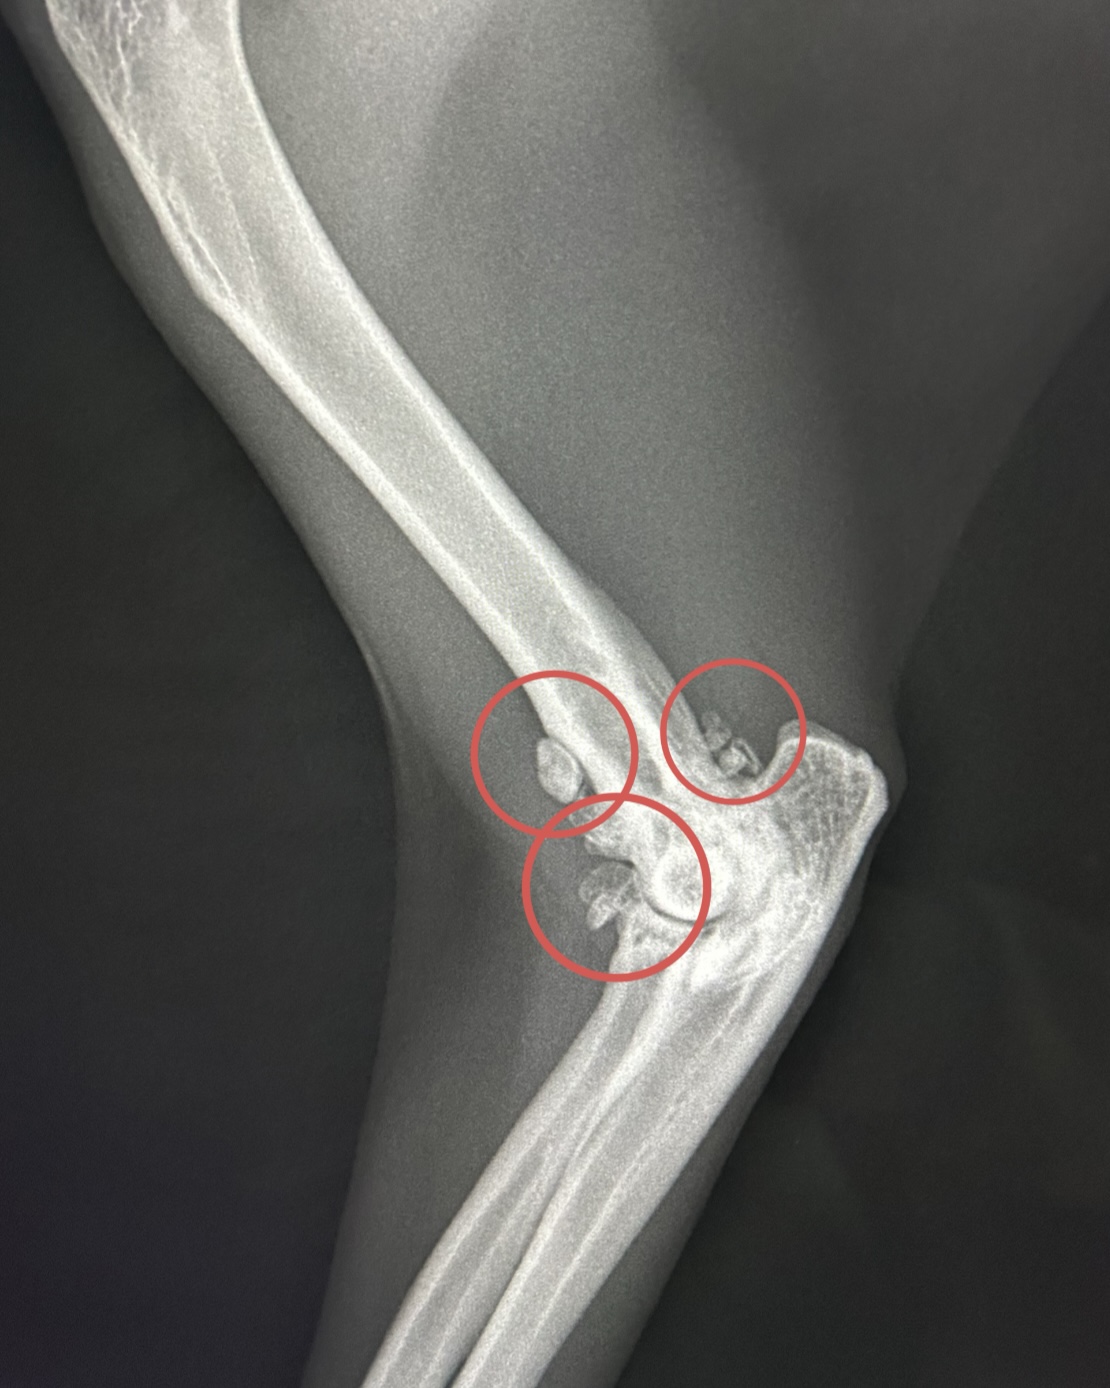

変形した関節(変形性関節炎)

正常な関節(〇は成長中のため亀裂がありますが正常な状態です)